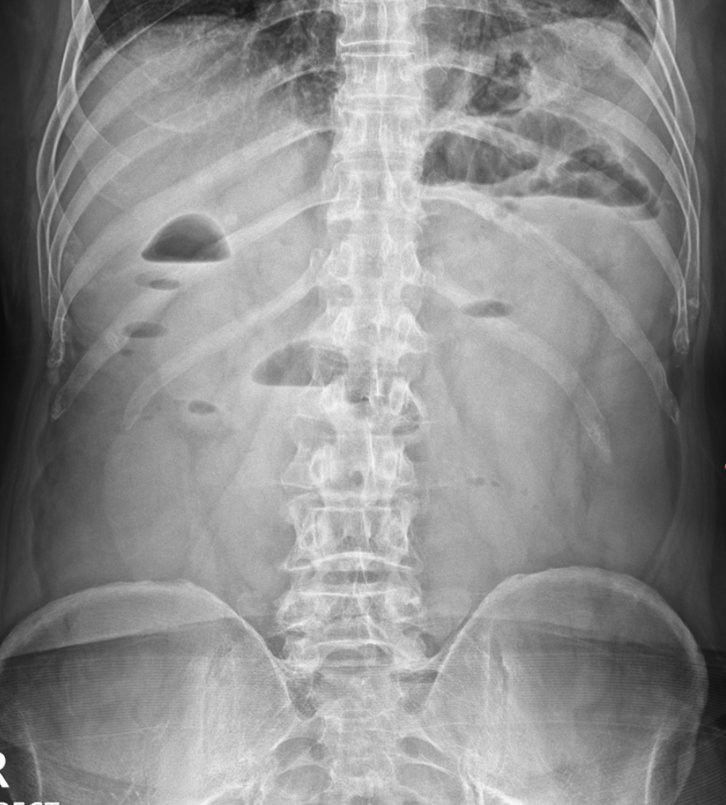

진료 후 기본 피검사로 확인을 하였고, 염증수치가 올라간 상태였고, X-RAY에서 소장의 가스가 저명하게 보였습니다. 단순 복부 엑스레이상에서 공기 액체층(air fluid level)이 관찰되는 사다리 징후가 확인되어, 장폐색 등의 가능성있어 추가 복부 CT를 시행하였습니다.

• 복부 X-ray: 사다리 징후 복부 X-ray: 사다리 징후